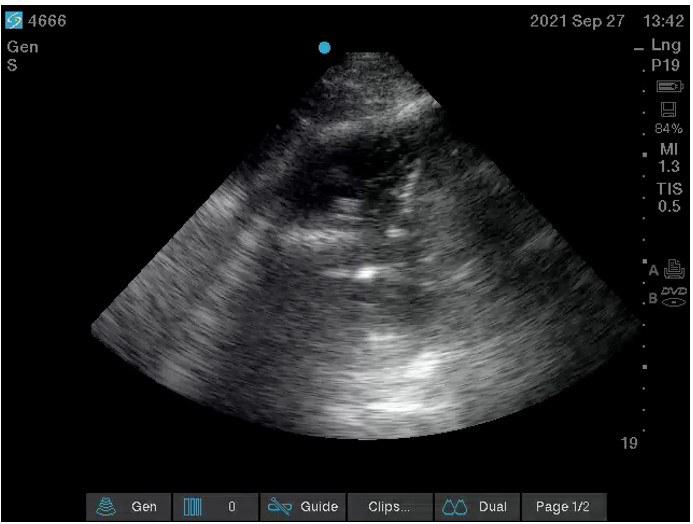

A 79-year-old male with a past medical history of Alzheimer’s dementia, chronic respiratory failure with tracheostomy and ventilator dependence, end stage renal disease, and atrial fibrillation is admitted to the intensive care unit from an outside hospital with septic shock. Urine cultures were positive for Vancomycin-resistant Enterococcus faecium and the tracheal aspirate was positive for Stenotrophomonas, Pseudomonas, and Proteus species. Chest x-ray demonstrated a right pleural effusion, which was present since outside hospital admission two and a half weeks prior. Decision was made to drainto rule out a source of persistent septic shock. Ultrasound guided thoracentesis was performed with ultrasound visualization during therapeutic aspiration. A total of 1400 cc of serous fluid was removed. After the procedure, the patient was briefly hypotensive, which resolved without intervention. Oxygenation remained stable. Pleural studies revealed a paucicellular lymphocytic transudate.